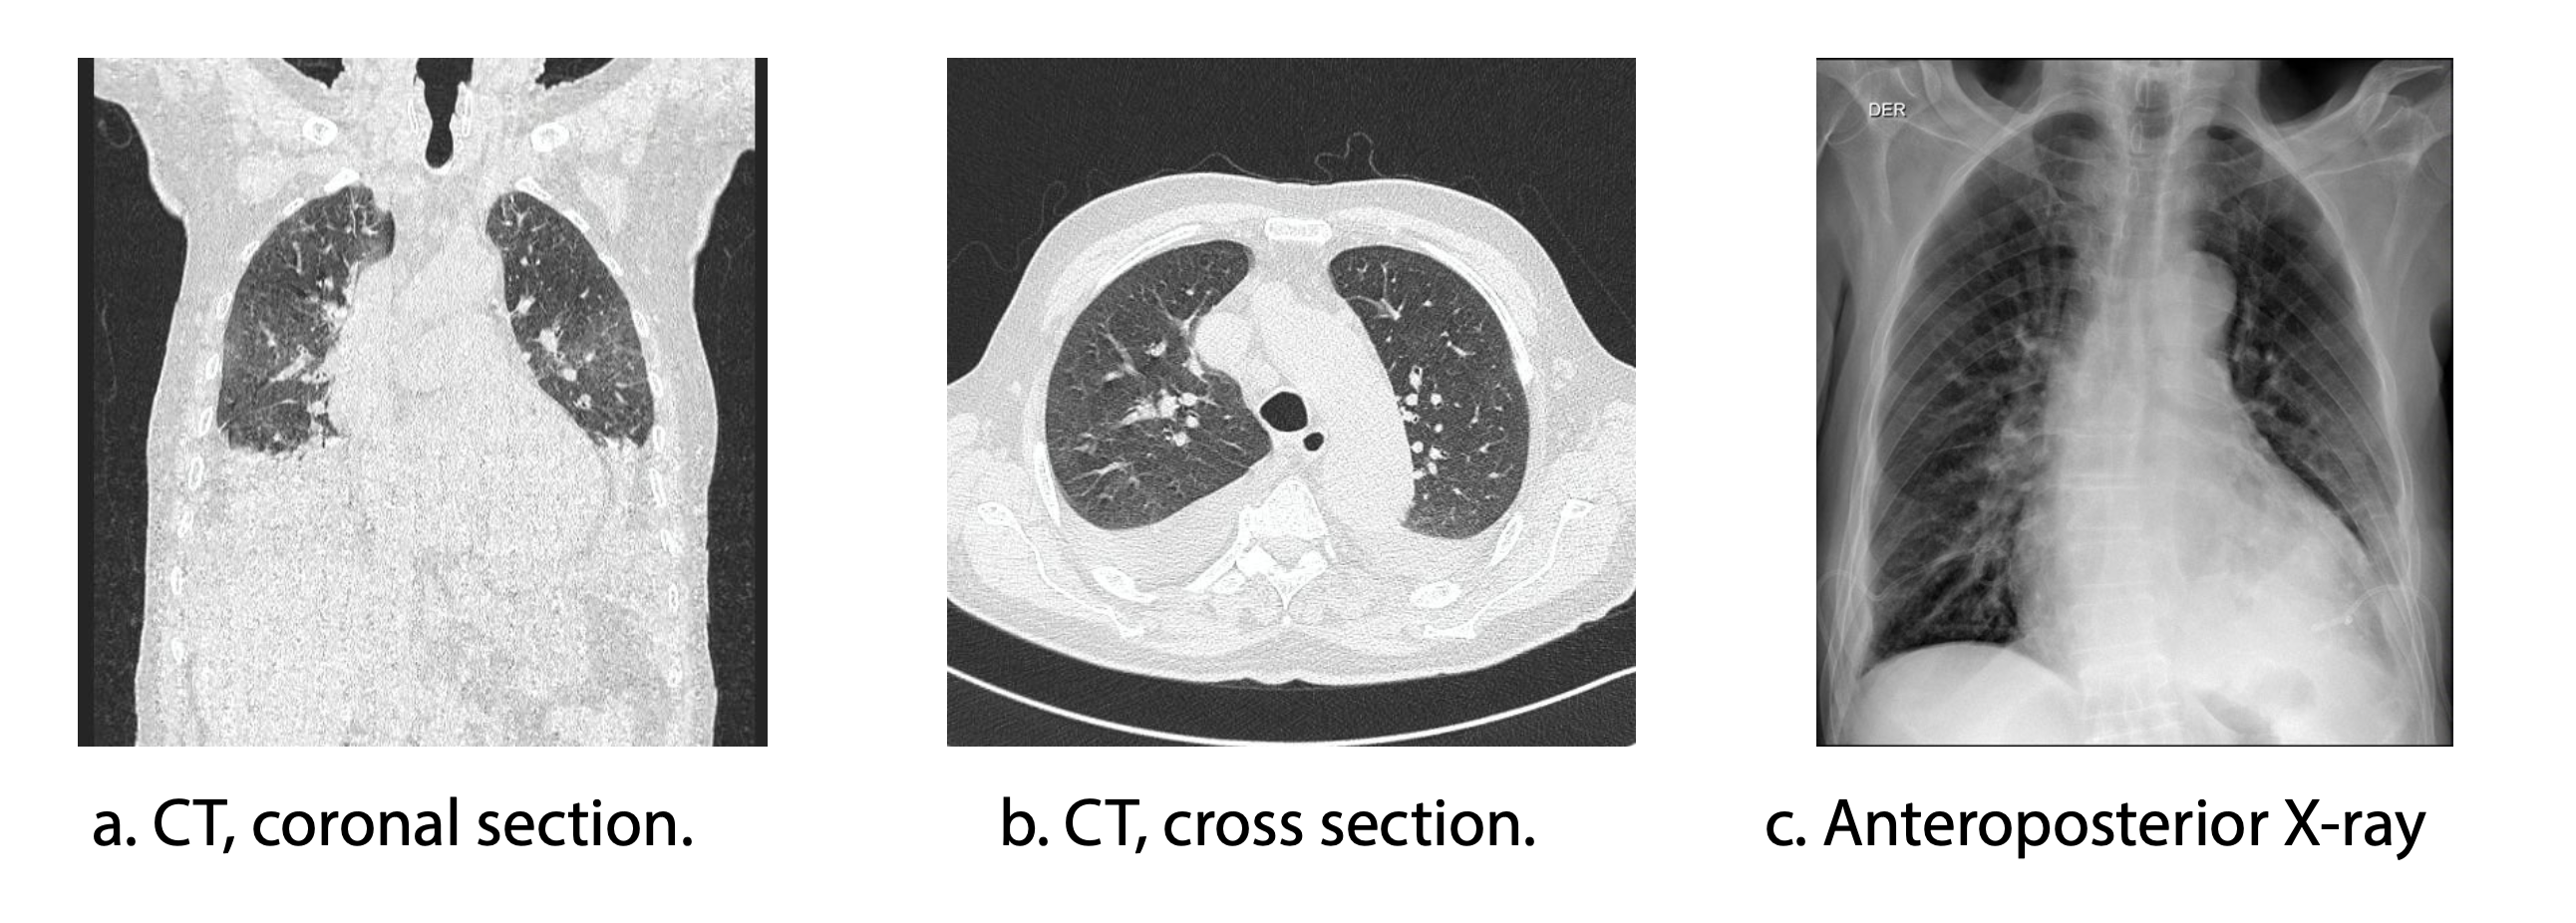

We present the case of an 83-year-old male patient with an incomplete COVID-19 immunization schedule and no influenza vaccination. His medical history included heart failure, severe aortic insufficiency, arterial hypertension, and a history of smoking. The patient was admitted to the emergency department on 01/13/23 with clinical symptoms of one month of evolution, including asthenia, adynamia, paroxysmal nocturnal dyspnea, orthopnea, and edema in the lower limbs. A diagnosis of decompensated congestive heart failure with acute pulmonary edema was established (Figure 1). A transthoracic echocardiogram performed on 01/21/2023 reported a left ventricular ejection fraction of 55%, a trivalve aortic valve with sclerosis and severe insufficiency, a 25 mm annulus, and mitral valve with moderate to severe insufficiency. Significant obstructive coronary artery disease was ruled out by cardiac catheterization on 01/26/2023. Subsequently, the patient was evaluated by the cardiac surgical board and was admitted to the protocol for transcatheter aortic valve implantation (TAVI).

Radiografía de tórax de ingreso 13/01/2023

Figure 1. Chest X-ray upon admission (01/13/2023)

To assess the pulmonary parenchyma (Figures 3a and 3b), a high-resolution computed tomography scan of the chest (HRCT) was performed on 02/01/2023. The findings were consistent with dilated cardiomyopathy, precapillary pulmonary hypertension, coronary artery atherosclerosis, and large bilateral pleural effusions, most likely secondary to heart failure and fluid overload. No radiological evidence of pneumonia was observed. Multiple mediastinal lymph nodes of indeterminate etiology were identified. Due to pleural effusions, whose origin was considered to be heart failure, diagnostic and therapeutic thoracentesis were performed with transudate criteria (02/03/2023).

Management of the COVID-19 and influenza coinfection included oral oseltamivir at a dose of 75 mg every 12 hours for 5 days, in accordance with IDSA guidelines. Corticosteroid therapy was contraindicated due to the confirmed influenza infection. The patient showed progressive clinical improvement (SaO₂ 96%, RR 16 rpm, and FIO₂ 24%) (Figure 3c), showing a favorable clinical evolution. However, despite this improvement, the severe cardiovascular condition persisted and required intervention. The decision to undergo cardiovascular surgery was carefully discussed in a multidisciplinary team consisting of cardiology and infectious disease specialists. Risks and benefits were evaluated, considering the high probability of complications given the recent history of two severe infections. Finally, it was decided to perform the surgical procedure (08/09/2023). Unfortunately, the patient experienced cardiorespiratory arrest during the procedure and died.

Imágenes radiológicas del tórax

Figure 3. Chest X-rays

Note: CT scan: computed axial tomography

The differential diagnosis of both diseases is complex, since the clinical manifestation of both conditions is similar16,17. In patients with COVID-19, blood tests often reveal leukopenia and lymphopenia, while chest CT typically shows ground-glass opacities. Unfortunately, these findings are also observed in influenza A and other respiratory viral infections18. However, there are cases described with different radiological findings19. Radiology has a key role in clinical decision making in patients with suspected COVID-1920,21.